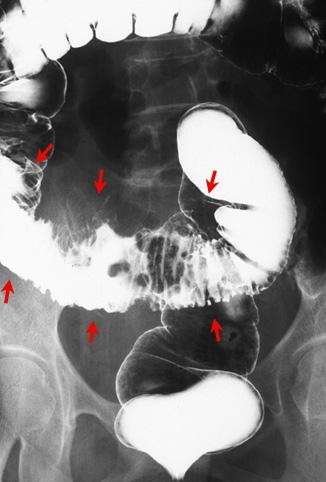

症例提示(所在地,施設名等): 東京都・ 国立がんセンター中央病院と九州がんセンターの共同作成

症例登録日 2008/05/20

画像ID:10471

疾患(病理主体)の分類悪性上皮性腫瘍/腺癌

部位(臓器別)大腸/S状

検査方法X-P

腫瘍の肉眼分類5型(分類不能)/

病変の最大径(ミリ)40以上

腫瘍の深達度ss(a1)